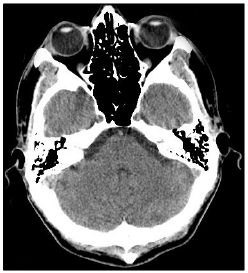

Analise a imagem de crânio a seguir.

É correto afirmar que a imagem anterior trata-se de uma: